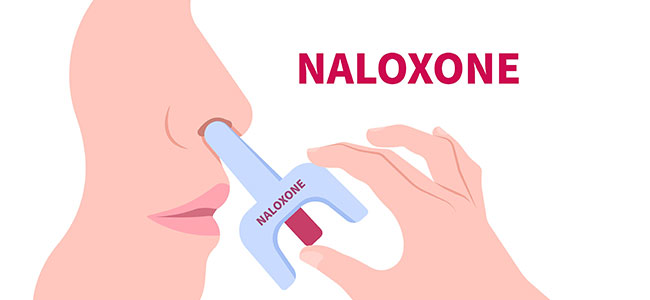

The product is an emergency treatment for opioid overdose.